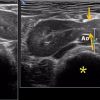

– Thận xoa trục, 2 cực dưới thận liên tục với nhau vắt ngang qua phía trước cột sống bởi nhu mô thận hay tổ chức xơ.

– Trên lát cắt dọc: không thấy rõ ranh giới cực dưới 2 thận.

– Trên lát cắt ngang qua đường giữa: 2 thận dính nhau, vắt ngang qua cột sống, phía trước động mạch chủ bụng.

– Có thể kèm theo các bất thường bất thường đường bài xuất, thận đôi, sỏi, nang thận hoặc u thận, sỏi gây giãn đường bài xuất.

=> Case lâm sàng 2: